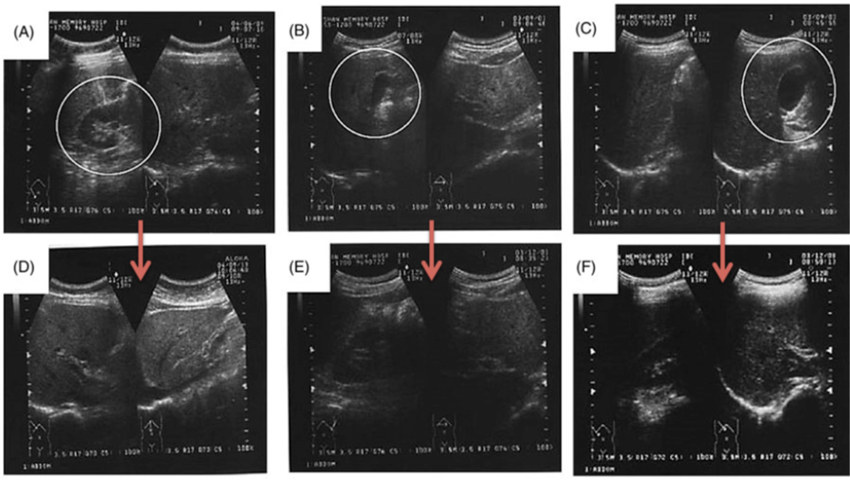

その他に、霊芝のカプセルを服用した後、GOTとGPT(肝臓や心筋、筋肉などの细胞の异常があるかどうかを判明する为)の数値も平均42%と27%に减少しました。また参加者の内、脂肪肝と胆嚢ポリープがあった3名は霊芝のカプセルを服用した後の腹部超音波検査では、元の症状がほとんど见られませんでした。(下の図に参照)

図(A)、(B)、(C)は参加者の腹部超音波検査の写真です。

(A)と(B)は軽い脂肪肝、(C)は胆嚢(たんのう)ポリープがありました。

(D)、(E)、(F)は6ヶ月间霊芝カプセルを服用した後の写真です。